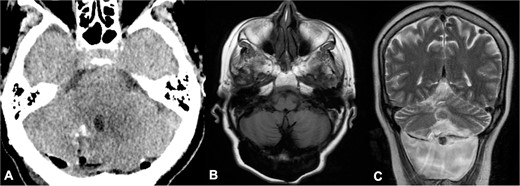

Postoperative head CT and 2-year follow-up brain MRI. (A) Axial view of head CT demonstrated complete resection of cysts; (B–C) 2-year follow-up brain MRI showed no recurrence of parasitic cysts in T1 axial and T2 coronal sequences and a cerebrospinal fluid fistula.

On neurological examination, ataxia persisted without new-onset neurological deficits. A recent 2-year follow-up brain MRI showed no recurrence of cyst formation and a cerebrospinal fluid fistula, which is currently awaiting surgical management (Figs. 4B and C).